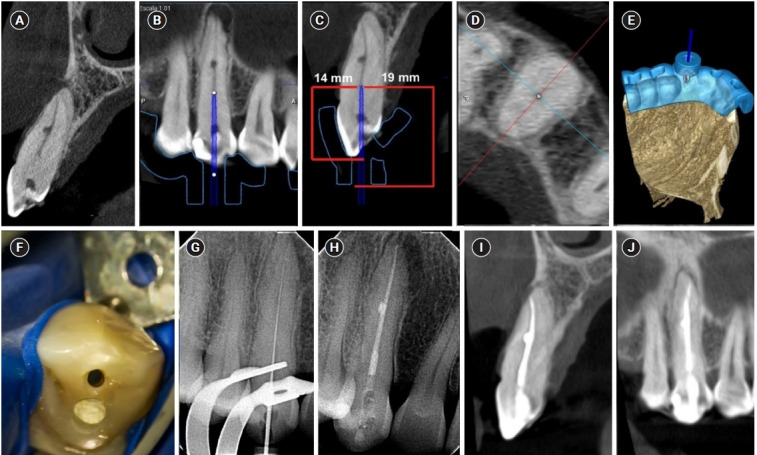

髓室和根管封堵术(PCO/RCO)是非手术治疗的难点。引导牙髓学(GE)旨在精确定位根管(RC)系统,同时尽可能多地保留颈周牙本质。GE包括将受影响牙齿的锥形束计算机断层扫描(CBCT)与上颌/下颌弓的数字印象相结合,允许通过三维(3D)静态导轨仔细规划到RC系统的钻孔路径。本文报告4例PCO/RCO牙伴内外根吸收及水平牙断的病例,均成功应用GE治疗。这些病例强调了使用CBCT进行GE治疗的临床和放射学上的成功,建立了这种技术作为管理矿化牙齿的可预测方法。

Pulp chamber and root canal obliteration (PCO/RCO) presents a challenge for clinicians when nonsurgical endodontic treatment is indicated. Guided endodontics (GE) aims to precisely locate the root canal (RC) system while preserving as much pericervical dentin as possible. GE involves integrating cone-beam computed tomography (CBCT) of the affected tooth with a digital impression of the maxillary/mandibular arch, allowing for careful planning of the drilling path to the RC system through a three-dimensional (3D) static guide. This article reports four cases of teeth with PCO/RCO, accompanied by additional diagnoses of internal and external root resorption and horizontal tooth fracture, all successfully treated with GE. These cases highlight the clinical and radiographic success of GE treatments using CBCT, establishing this technique as a predictable approach for managing mineralized teeth.